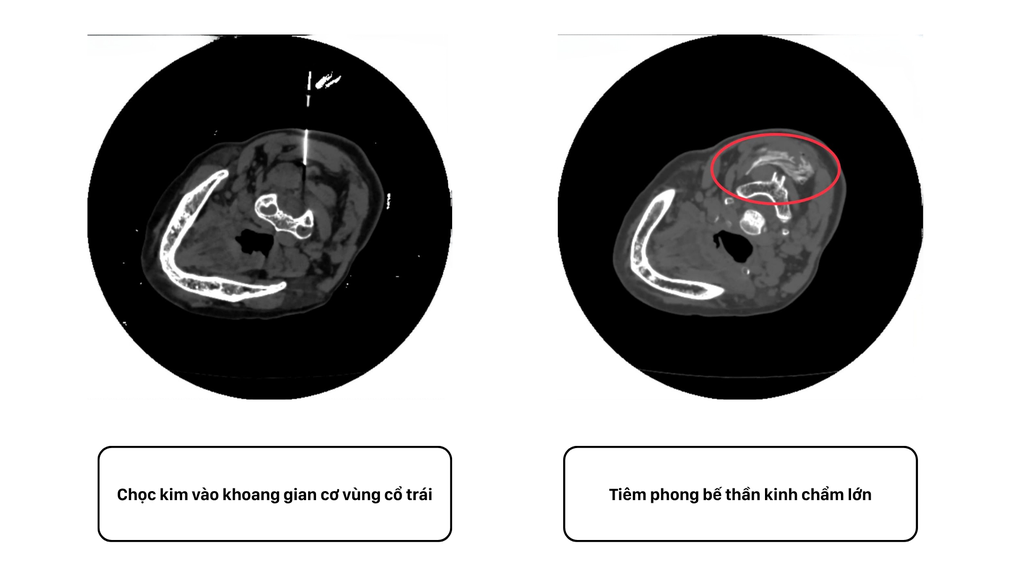

Pod vedením moderního CT skeneru lékař zavedl tenkou jehlu obsahující směs anestetika a protizánětlivých léků přímo do velkého týlního nervu (Arnoldova nervu). Lék, když byl umístěn na správné místo, blokoval signál bolesti z nervu do mozku.

Snímek dráhy léku skrz jehlu do týlního nervu pod kontrolou CT vyšetření (Foto: BVCC).